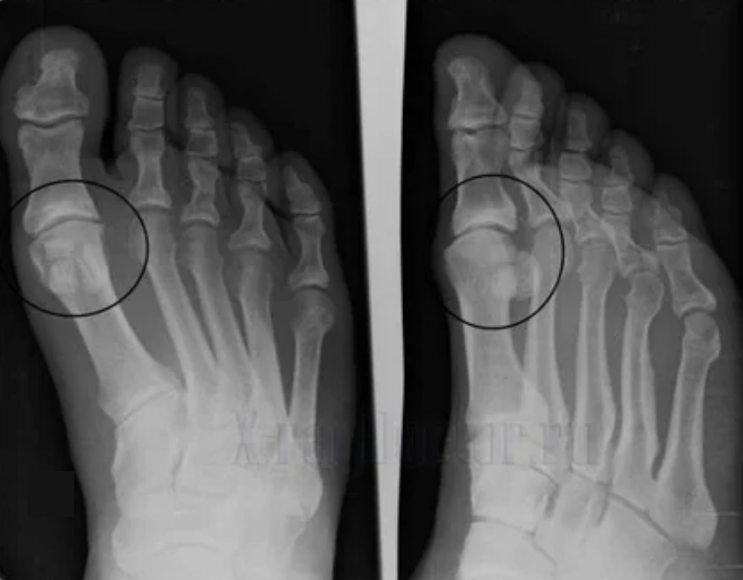

Diagnoosi tegemiseks uurivad reumatoloogid patsiendi kaebusi ja määravad X -RAY uuringu. Kõige sagedamini kasutatakse radiograafiat kahes projektsioonis. Arst uurib düstroofiliste häirete esinemist hüaliini kõhre ja luuühenduste korral. Kui liigesevahe on vähenenud, luud deformeerutakse või lamestatakse, kõhre pinnal on tsüstilisi moodustisi, osteofüüdid on ilmsed artroosi tunnused. Vastuse ajal näitab artroos liigese ebastabiilsust: jäsemete telg ja subluksatsioon on häiritud.

Sageli ei suuda X -RAY -pilt anda täielikku teavet liigese seisukorra kohta. Põhjalikuma uuringu jaoks on ette nähtud kompuutertomograafia, see on efektiivne luude uurimiseks. MRI -d kasutatakse sagedamini pehmete kudede uurimiseks.